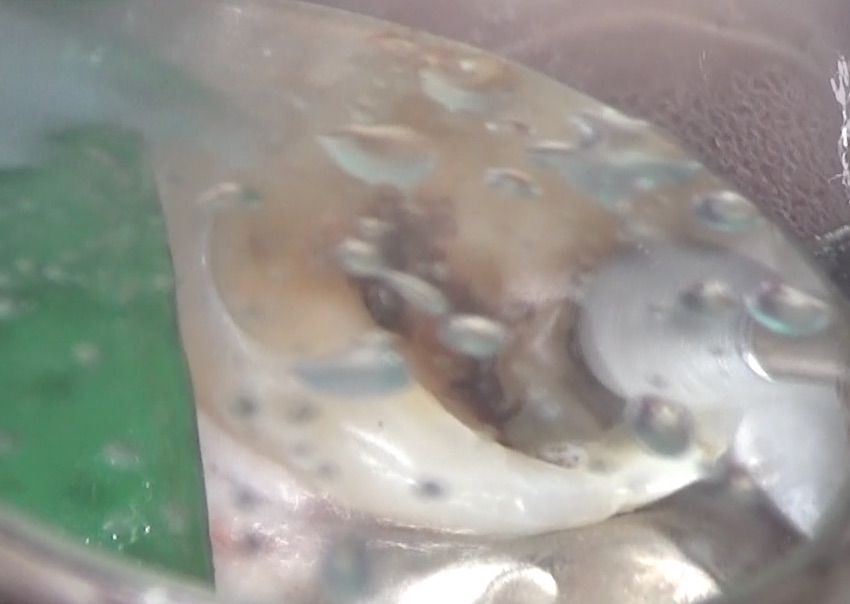

虫歯を取り除いています。

キレイに取り除くと、歯の内部から、出血をなにやら白い体液が一緒に出てきました。

触ると、ネチョネチョしています。

これは膿でした。この写真は、その膿と出血が混ざっているところです。